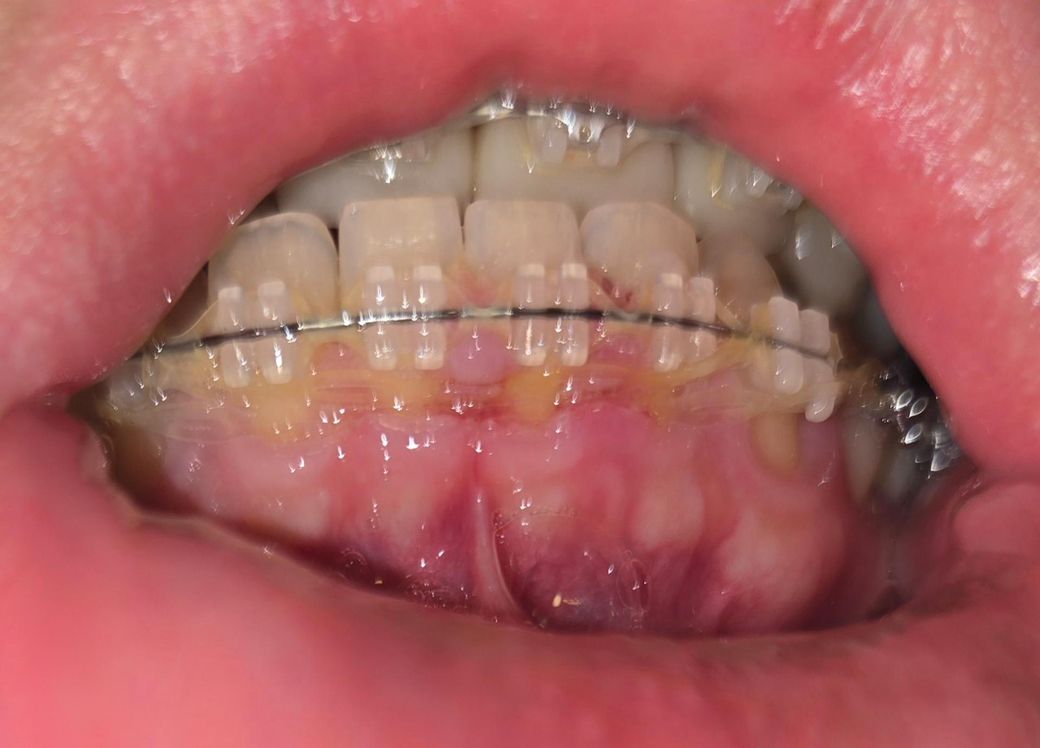

치과 교정중인데 이게 정상적인 치료가 맞나요??

보통 파워체인을 치아에 부착된 브라켓에 연속으로 연결하잖아요?

근데 최근 잇몸이 브라켓 위로 튀어나올정도로 너무 붓고 그래서 자세히 살펴보니

정상적으로 연결된 파워체인과는 별개로 또 다른 파워체인을 끼웠는데

파워체인을 34번 44번 치아쪽에만 끼우고 31, 32, 33, 41, 42, 43번 치아쪽은 브라켓 위에 끼운게 아니라

브라켓 아래쪽으로 그냥 잇몸 위를 지나가게 둬서 파워체인이 잇몸 속으로 파고들었더라구요

제가 전문 지식이 있는건 아니지만 도저히 정상적인 치료같지는 않은데 이런 경우가 있나요?

• 1번 째 사진